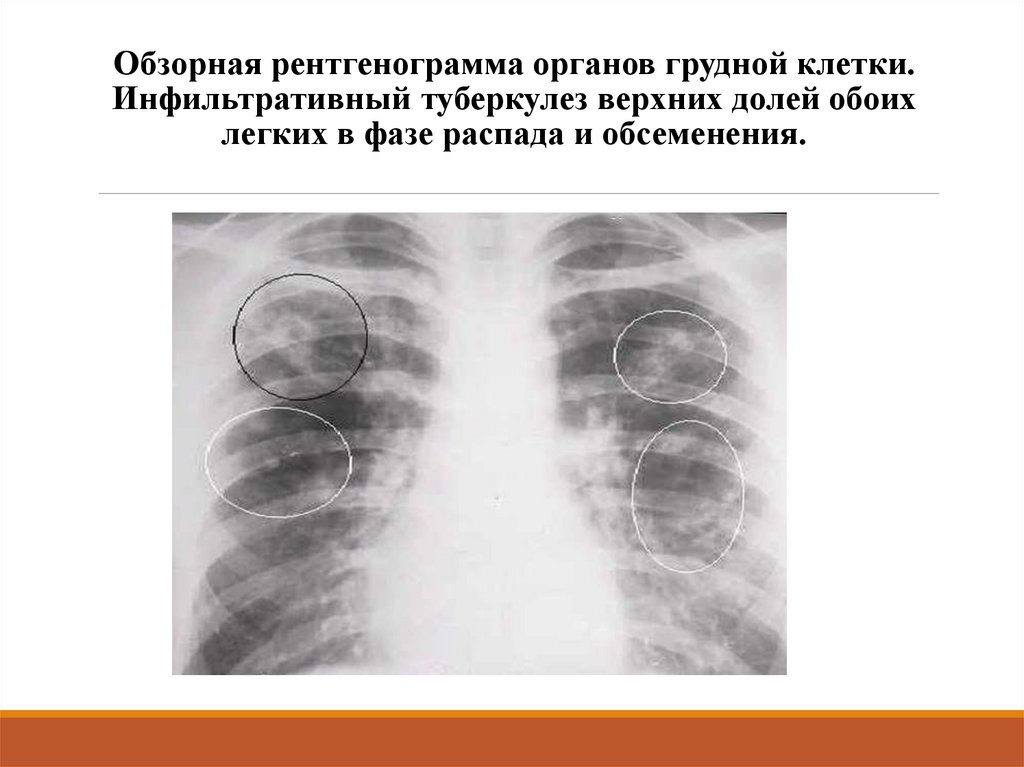

Очаговый и инфильтративный туберкулез презентация - 94 фото